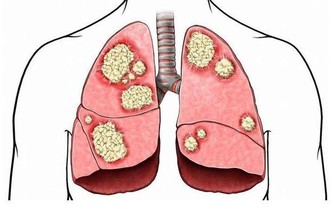

膽固醇高的危害

膽固醇的正常值是0-5.2mmo/L(0-200mg/dl),超過這個值就是表現為膽固醇高,膽固醇高的危害主要有:

1、會加快前列腺癌的生長速度,會引發腎衰竭脂類的腎臟疾病。

2、會減少人的壽命,尤其是男性的壽命同時和血管有關的中風機率會隨著增加。

3、會阻塞心臟動脈和使其變窄,更容易引發心髒病。

4、會使骨質疏鬆症的可能性變高,同時過多攝入膽固醇可導致牙周病、牙和牙隙之間的溝隙會擴大。

由此可見,膽固醇高的患者要及時到醫院進行治療,以免延誤病情,導致病情惡化。